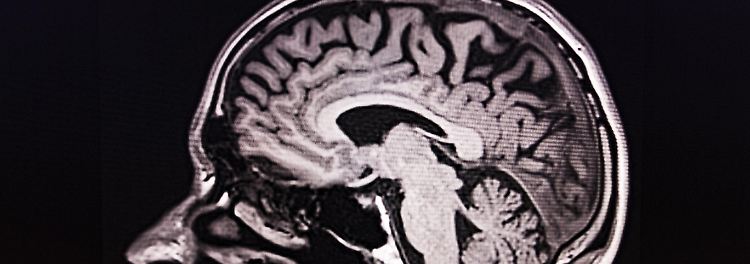

Kinder schützen Elterngehirne vor Alterserscheinungen